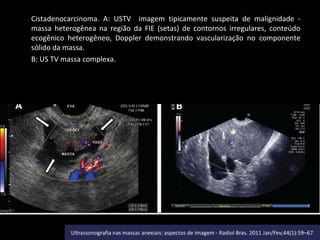

Cistadenocarcinoma. A: USTV imagem tipicamente suspeita de malignidade massa heterogênea na região da FIE (setas) de contornos irregulares, conteúdo

ecogênico heterogêneo, Doppler demonstrando vascularização no componente

sólido da massa.

B: US TV massa complexa.